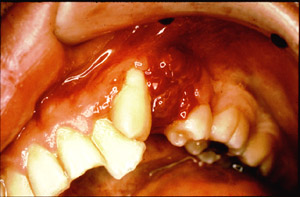

Congenital Epulis (Nerve Cell Tumor)

Photo 2